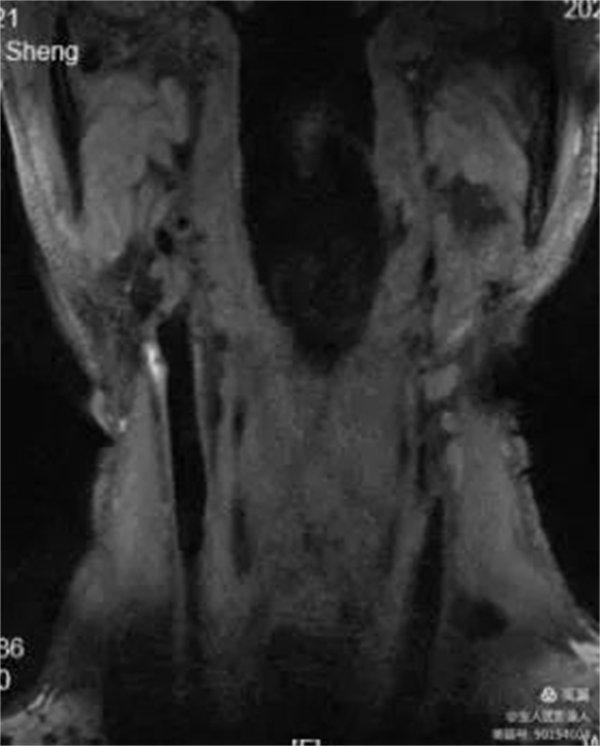

67岁男性,颈动脉斑块成像显示:颈总动脉及颈内动脉粥样斑块,偏心性生长伴出血,MRI诊断不稳定性斑块。

常规TOF-MRA显示颈动脉管腔明显局部狭窄

冠状位显示颈内动脉起始段管壁增厚,呈高信号

增强明确管壁增厚原因

平扫和增强对比明确管壁增厚病因,提示:粥样斑块,并内出血,多系不稳定斑块